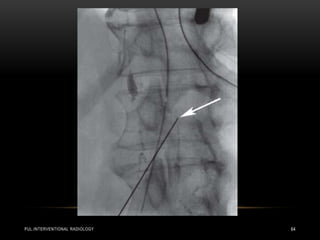

• Today there are several radiological treatments that can be used

in both traumatic and non-traumatic chylothorax .

• Much more experience is available for percutaneous

embolization of the thoracic duct , which can be performed as

an alternative to thoracic duct ligation and can be performed in

both adults and children .

• Embolization has a much higher success rate: if the thoracic

duct can be intubated successfully, the procedure is successful

in well over 90% of cases